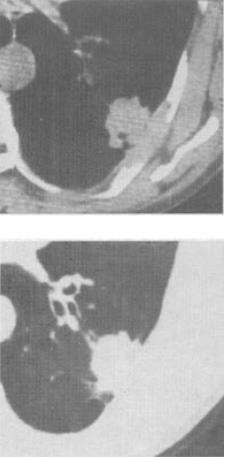

- 单项选择题1、 女,65岁,胸透发现左肺病灶,CT检查如图,最可能的CT诊断为()。

A、慢性炎症

B、淋巴瘤

C、炎性假瘤

D、中心型肺癌

E、周围型肺癌